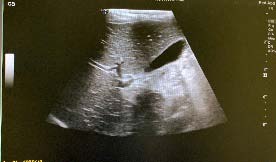

? Dedifferentiated liposarcoma ? Myxoid liposarcoma ? Pleomorphic liposarcoma ? Myxoid pleomorphic liposarcomaIn atypical lipomatous tumour/well differentiated liposarcoma adipocytic variant consists out of cells that vary substantially in size as well as cells that have Dedifferentiated liposarcoma can arise as a synchronous lesion in 90% of cases and as metachronous lesion in 10% of cases 6 . These tumours exhibit a wide morphological spectrum and histologically show areas of high grade, poorly differentiated sarcoma resembling high-grade myxofibrosarcoma, fibrosarcoma, malignant solitary fibrous tumour or pleomorphic sarcoma not otherwise specified. Dedifferentiated liposarcomas can be of variable histological grade 5 . Dedifferentiated liposarcomas is an aggressive disease, arising most commonly in the retroperitoneum and is associated with high rates of local and metastatic recurrence and disease specific mortality 7 Use of the term atypical lipomatous tumour is determined by tumour location and resectability. In locations such as the retroperitoneum, it is usually impossible to obtain a wide tumour free surgical margin of more than 2cm, thus local recurrence is common and leads to mortality, seen in the absence of dedifferentiation or metastases The introduction of computed tomography (CT), magnetic resonance imaging (MRI), and ultrasonography have greatly enhanced our capability to make the diagnosis of abdominopelvic neoplasms and determine and direct treatment, as well as observe the progress of the neoplasm and effect of treatment over time. Identification of a retroperitoneal mass at imaging is a challenging task for radiologists, however the presence of fat within a retroperitoneal lesion is helpful in refining the differential diagnosis 9 ? On ultrasound appearance it is hyperechoic and may demonstrate posterior acoustic shadowing . It is easy to recognize fat within a lesion due to its characteristic imaging appearance:

Large feeding arteries of a hypervascular to the of origin A CT image of a lipoma will reveal a welldefined homogenous mass with fat attenuation. Areas of soft-tissue attenuation may be seen within the tumour and may represent fat necrosis, septa or normal adjacent structures. If a predominantly solid soft-tissue component or adjacent organ invasion is present, a liposarcoma should be suspected. The imaging characteristics of liposarcomas differs, depending on the histological subtype.

Well-differentiated liposarcomas appear as well defined predominantly fat-containing lesions with minimal soft tissue attenuation and commonly contain septa -the appearance may be indistinguishable from a lipoma 9 and therefore aretroperitoneal purely fatty lesion should be considered a liposarcoma rather than a lipoma until proven otherwise with histological confirmation 10 11 . Dedifferentiated liposarcomas appear remarkably similar to well-differentiated liposarcomas of CT imaging, and dedifferentiation is suggested by focal nodular non-lipomatous regions larger than 1 cm 12 Surgery is the mainstay of treatment for nonmetastatic retroperitoneal sarcoma 8 . If possible, macroscopically complete resection of tumour should be aimed for and this can lead to radical surgery requiring en-bloc removal of adjacent structures. If the pre-treatment diagnosis can be made with certainty, based on radiologic and clinical findings and complete resection is deemed possible, pre-treatment biopsy is not advised and has no value 13 . If radiologic investigations suggest a pathology that does not require primary surgery (e.g. lymphoma, Ewing Sarcoma, GIST) or the incomplete resection is expected, biopsy will be necessary to plan alternative treatment. Image guided core biopsy is advised and preferred over open or laparoscopic approaches, which may be associated with tumour spillage and compromise future surgical strategy by altering tissue planes 14 The removal of the entire tumour with a margin of normal tissue is usually not possible in large retroperitoneal liposarcomas due to the presence of adjacent large vessels, nerves and bony structures, leading to local recurrence in the abdomen, which constitutes the cause of death in three out of four patients . 15 ii. Radiation Therapy . High grade, dedifferentiated tumours are at a higher risk to recur and spread systemically, so even if extensive surgery with adequate margins is achieved, the prognosis remains dismal, querying the fact whether a patient should be exposed to the morbidity of extensive surgery if the mortality in dedifferentiated liposarcoma remains high irrespective of treatment.